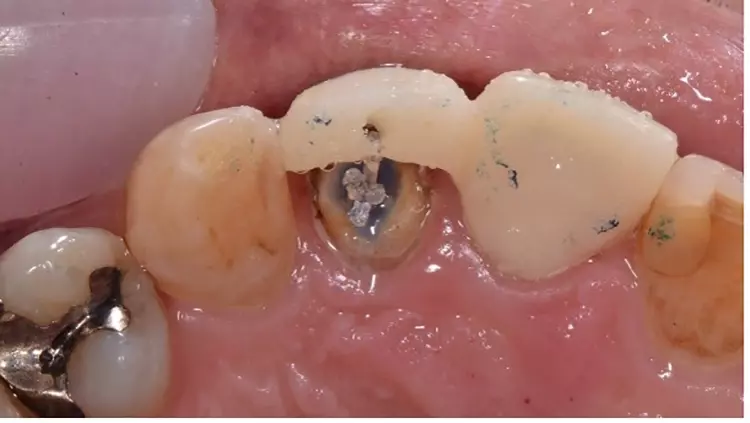

Nachfolgend wurde die Wurzelkanalbehandlung an beiden Zähnen 21 und 22 revidiert und der Zahn 21 mit einem Glasfaserstiftkernaufbau wiederaufgebaut. Zahn 22 wurde im Wurzelkanal oberhalb der Guttapercha-Wurzelfüllung adhäsiv verschlossen und eine Gummiligatur darin vorerst spannungsfrei mit einem adhäsiv haftenden Glasionomerzement, zur farblichen Kontrastierung, eingeklebt. Anschließend wurde ein verblocktes Provisorium der Zähne 21 und 22 auf dem Zahn 21 adhäsiv befestigt und das Brückenteil 22 außer Kontakt geschliffen und nach basal zur Wurzel frei gelassen (Abb. 3). Durch die adhäsive Befestigung wurde das Risiko einer Dezementierung der provisorischen Versorgung möglichst geringgehalten.

Die Aufnahme von palatinal zeigt dabei die Kontaktpunktverteilung und auch das Platzverhältnis zwischen Stumpf und basaler Gestaltung des Brückenglieds (Abb. 4). Eine regelmäßige Kontrolle des Patienten im Abstand von jeweils 1 Woche für eine Gesamtdauer der Extrusion von 3 Wochen wurde in diesem Fall in Abhängigkeit von der Zahnbeweglichkeit als angemessen empfunden. Es musste hierbei ein zusätzlicher Ferrule-Effekt von ca. 1,5 mm generiert werden.